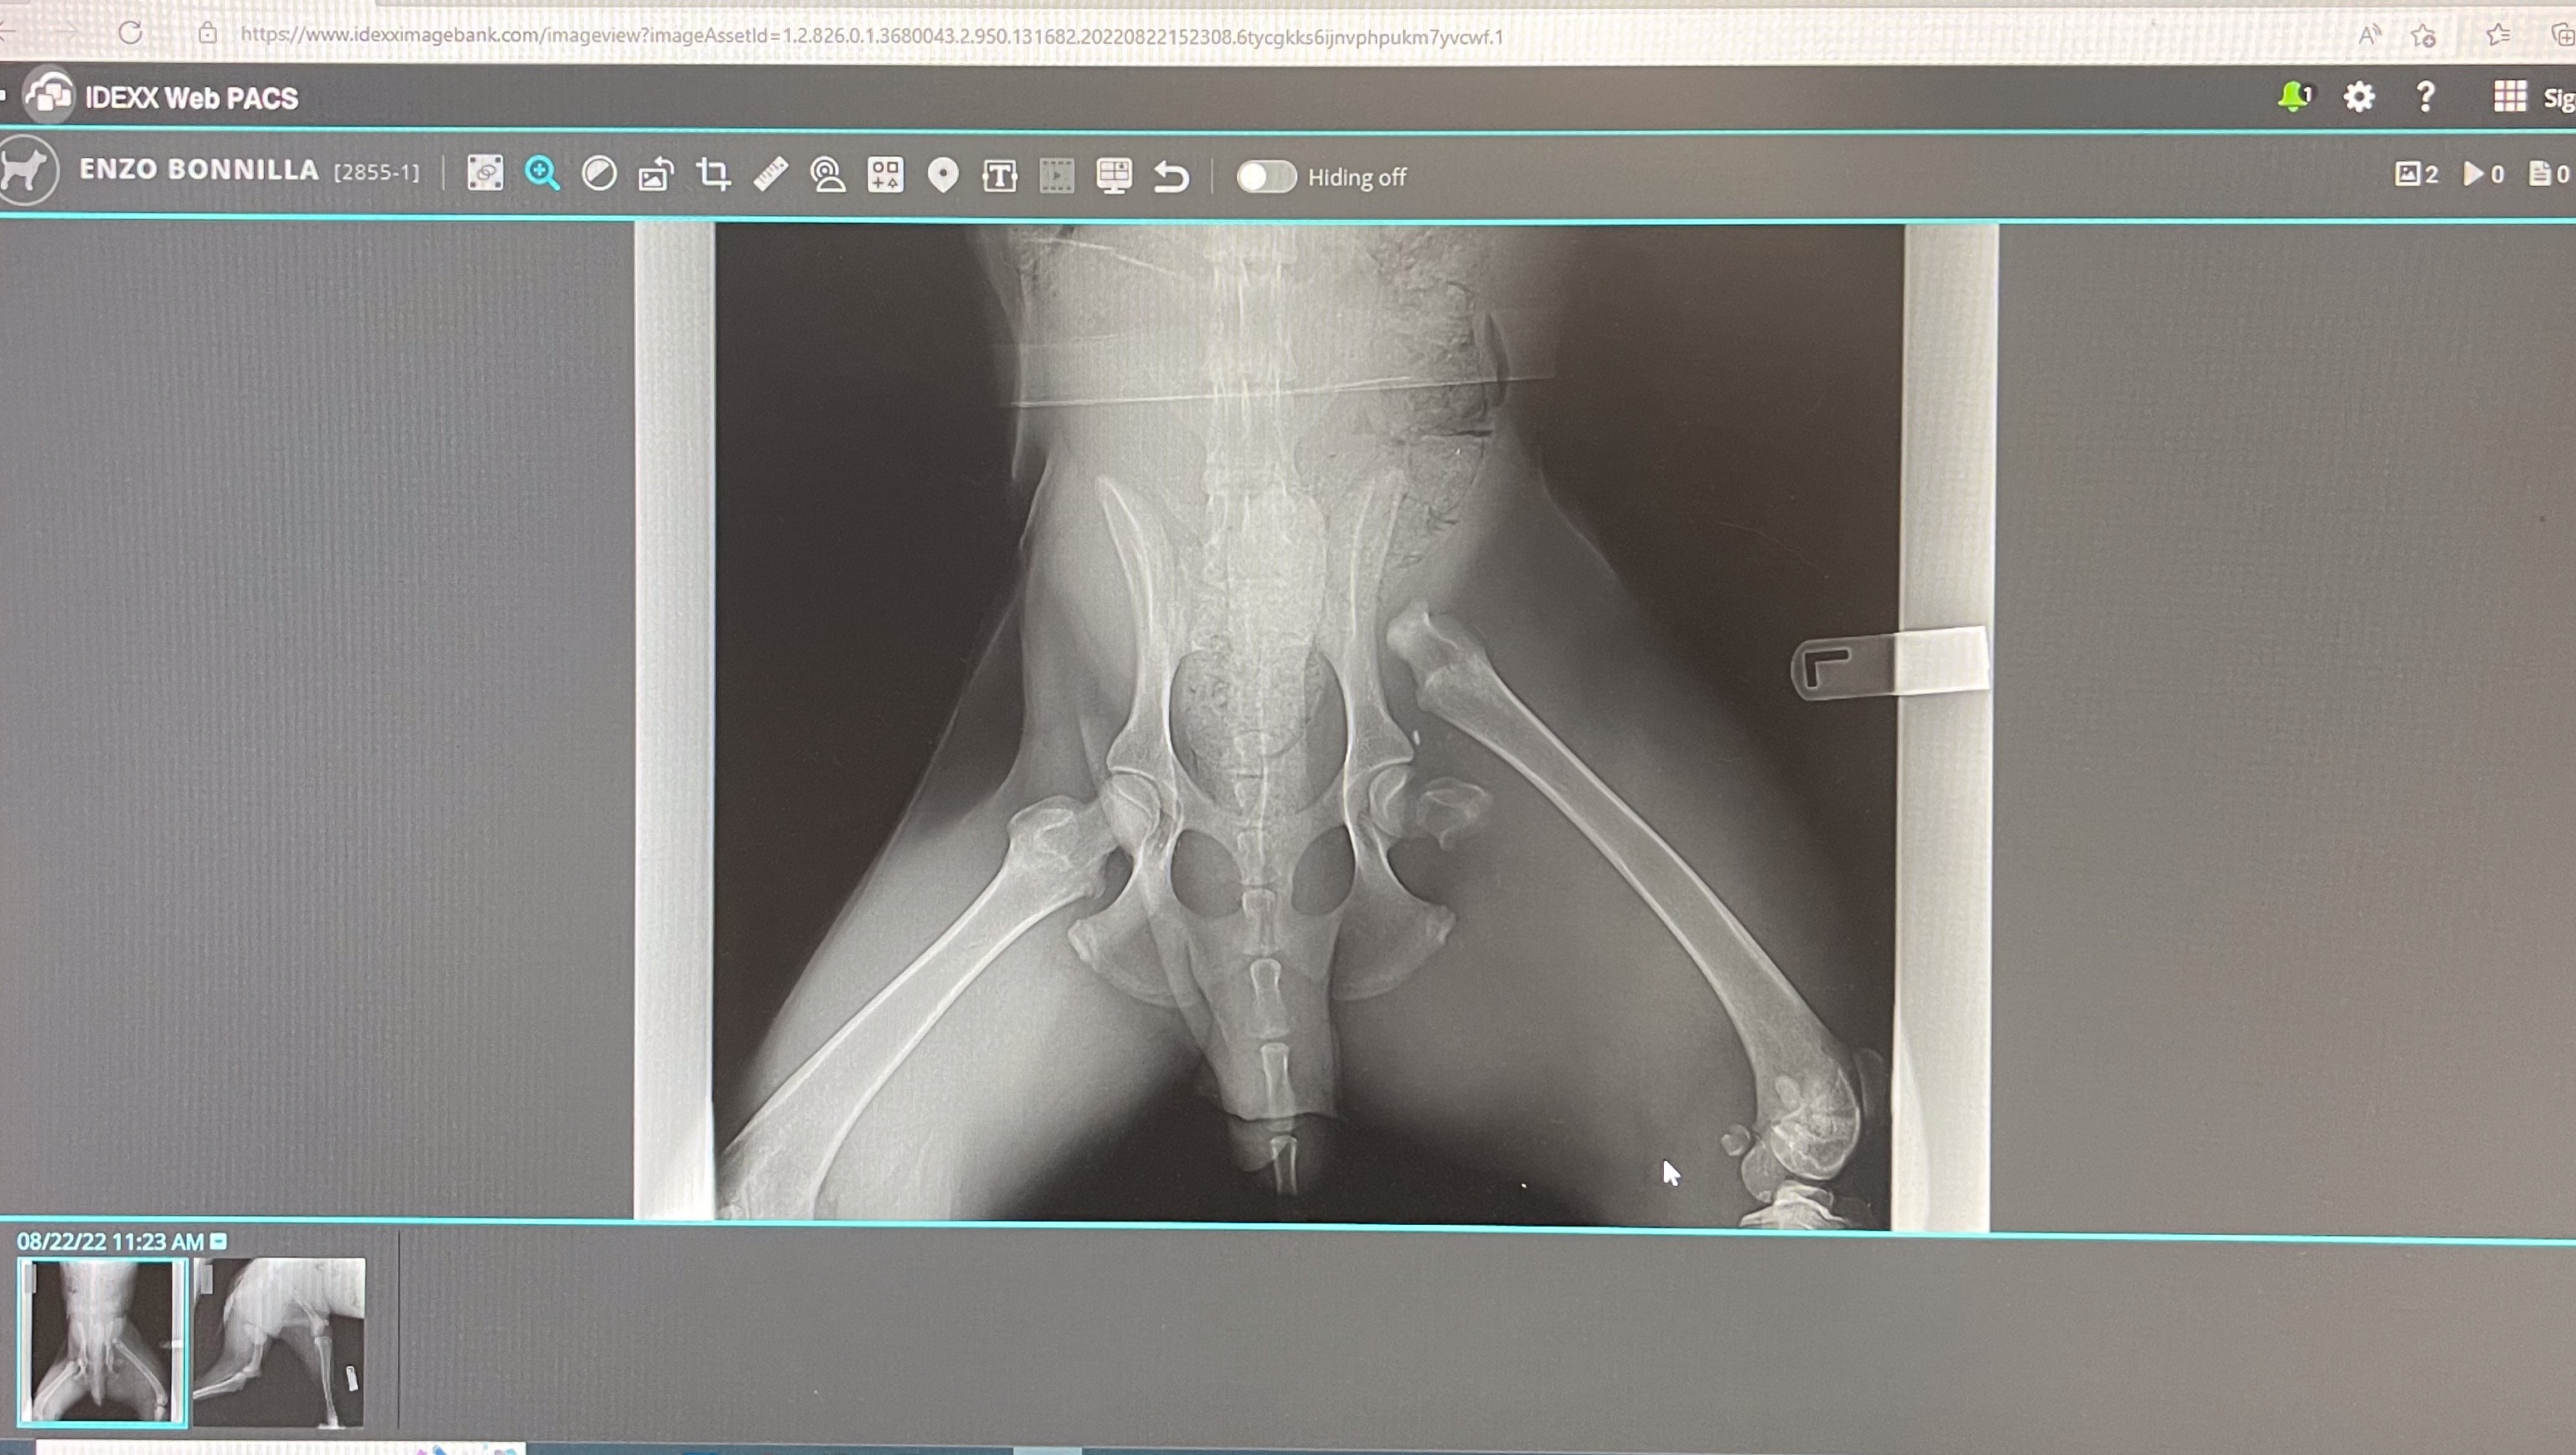

I am devastated to have to write the words that my best friend of 1 year is in trouble and desperately needs my help. My Enzo is suffering, and my hands are tied. My baby escaped my yard and wandered off. I searched for hours for him and was unsuccessful in finding him. I checked the door every hour for him, praying and hoping he'd return. Amazingly, around 6 am, I saw him on the porch. Enzo was in such severe pain to what appeared to be caused by an attack. I immediately took him to the vet, only to learn that he had been hit by a car and possibly dragged some feet. It was a miracle that he even found his way back to the porch. He is in need of immediate emergency surgery to fix his broken hip. I could only afford to get his wounds cleaned, stitched up, and brought home to rest. Please, help me help Enzo receive the surgery he needs so he can live his life to the fullest. I thank you dearly for any support you can provide by donating. I pledge to donate any funds donated for Enzo that are not needed or used to another unfortunate person and their pet in need of emergency surgery.